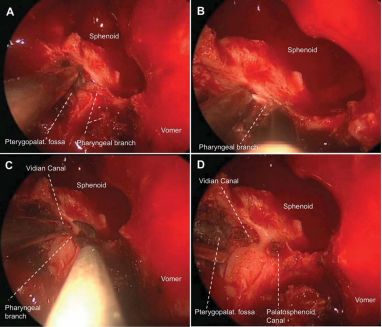

图示。0度镜下新鲜尸头标本的左侧鼻腔解剖。A、暴露腭骨垂直板,注意蝶腭孔由腭骨蝶突和眶突围成;B、显露腭鞘管的鼻咽顶壁开口及其内穿行的上颌动脉的咽支。请留意翼腭窝内的腭鞘管开口;C、磨除腭鞘管前内侧壁(即部分腭骨蝶突)暴露管内容物,请留意其与蝶犁缝之间的联系;D、离断咽神经血管束并外推,可显露翼管开口。注意腭鞘管的上、外侧壁为蝶窦底壁,没有蝶骨鞘突的参与。在翼腭窝内,腭鞘管开口于翼管的内侧;E、从后往前磨除腭鞘管,暴露其外侧的翼管神经(F)。

图示。0度镜下右侧翼突进路的术中图片。A、磨除部分腭骨蝶突可见上颌动脉的咽支从翼腭窝向鼻咽顶壁走形;双极烧灼(B)并离断(C)咽神经血管束;D、外推翼腭窝内容物可以辨认翼突根部的翼管。同时可看到腭鞘管嵌入蝶骨。Pterygopalat = Pterygopalatine; Palatosphenoid = Palatosphenoidal.